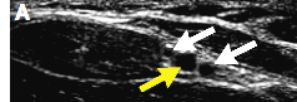

(2)穿刺部位的选择:保证探头在5~13 MHz的频率下开始评估血管。确保探头左侧所处部位的显影在屏幕左侧。自腕部起,对前臂侧面进行横向扫描,在桡骨茎及桡侧腕屈肌之间确定桡动脉及伴随静脉。必要时应用光压鉴别动脉及静脉(静脉是塌陷的,而动脉是充盈的),见图3。

图3.光压作用鉴别动、静脉

桡动脉(A,下方箭头)横断面可见有静脉伴随(白色箭头)。超声探头的光压可引起静脉塌陷但不影响动脉,动脉仍可见(B,箭头)